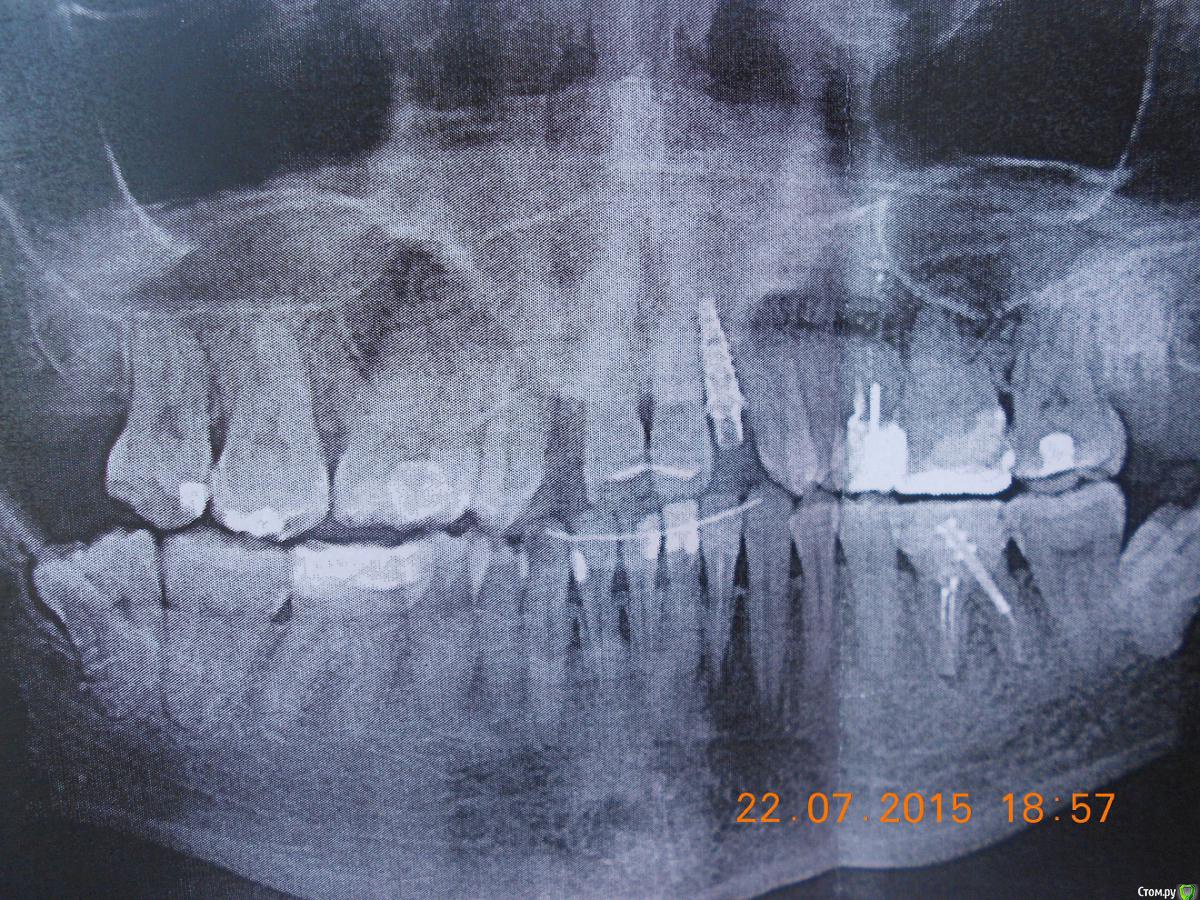

Добрый день, прошу проконсультировать, как поступить в моей ситуации.Прикус как могла сфоткала, сейчас проблема в отсутствии 2х верхних резцов, на их место поставила импланты-но они не прижились-в качестве наиболее вероятной причины выдвигают-недостаточность места, близость к корням соседних зубов.Возможно ли в моем случае ситуацию исправить брекетами.Прикус по-моему неправильный, ВЧ узкая, перекрытие НЧ есть в р-не передних зубов и задних, в середине картина не очень.Возможно ли немного расширить ВЧ. И беспокоит не будут ли смещаться зубы на место отсутствующих?Сейчас на месте одной из двоек съемная бабочка на месте другой имплант который нужно удалять.

У Вас было уже лечение с применением брекетов, правильно? Ситуация непростая , судя по снимку ОПТГ места и правда маловато для боковых резцов, но снимок не очень четкий. А насчет исправления прикуса -этих снимков недостаточно , чтобы уверенно говорить о плане лечения. Можно с помощью брекетов и миниимплантатов создать больше места для боковых резцов, НО ЭТО ДОЛГО ( очень долго, хорошо , если за 2 года ). Быстрый вариант -мостовидный протез .

Вы правильно обрисовали картину. У вас дефицит места для  "двоек" ,  также перекрестный прикус слева  (справа Вы не показали) (обратное перекрытие зубов, что чревато для сустава.) Также отсутствие верхнего бокового зуба ("пятерка"),  также ретенированные восьмерки (их надо удалять), ну и качество пролеченных зубов оставляет желать лучшего.